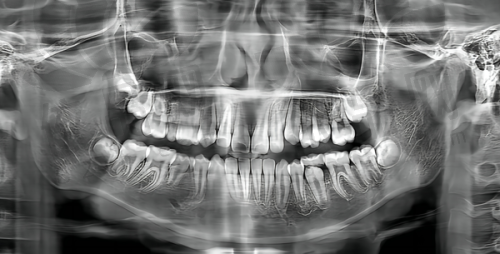

成都安玉牙种植医院是一家正规的私立牙科医院。它始建于1991年,其前身为卫生部口腔种植科技中 心,有着“现代口腔种植医学的发源地和摇篮”的美誉。经过30多年的发展,已成为以牙齿种植技术为特色的口腔专科医院,在海内外都有较高的有名度,能够为广大顾客提供高品质的医疗服务。

在老年人种牙领域,成都安玉牙种植医院经验多、技术不错。它由陈安玉医生团队组建,医生们擅长处理各种复杂的牙齿缺失情况,能为老年人量身定制个性化的种植方案。而且,医院采用精良的种植牙技术,像引导骨再生术、上颌窦提升术、即刻种植牙即刻修复术等,为顾客提供优质的种植解决方案。